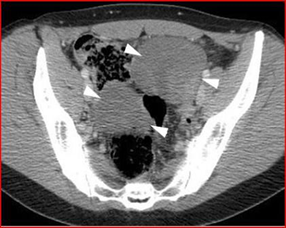

There are rare cases in the literature describing ovarian lymphoma which, although mimicking ovarian cancer, are diagnosed preventively, avoiding surgery. This aspect is well highlighted by Cyriac et al [11] who described the presence of Burkitt’s lymphoma in a 13-year-old patient, who, thanks to the use of CT, which highlighted the bilateral solid masses with peritoneal and omental deposits and the subsequent biopsy which detected positivity for CD45, CD20, CD10 and CD79 (Figure14), she was subjected to the LMB 89 therapeutic protocol obtaining a complete remission of the masses and remaining stable in the following 6 months of follow-up -up. Given the young age of the patient, this case highlights how chemotherapy treatment of lymphoma alone can avoid radical surgery. Another example of correct diagnosis is reported by Yamada [35], who describes a case of ovarian malignant lymphoma manifesting as advanced ovarian cancer.

Figure 14: The CT image highlights two solid and bilateral ovarian masses, with the presence of omental deposits and peritoneal implants. The immunohistochemical image obtained after biopsy highlights a proliferation of atypical lymphoid cells with little cytoplasm, nuclei with aggregated chromatin and many small nucleoli showing a high mitotic count.